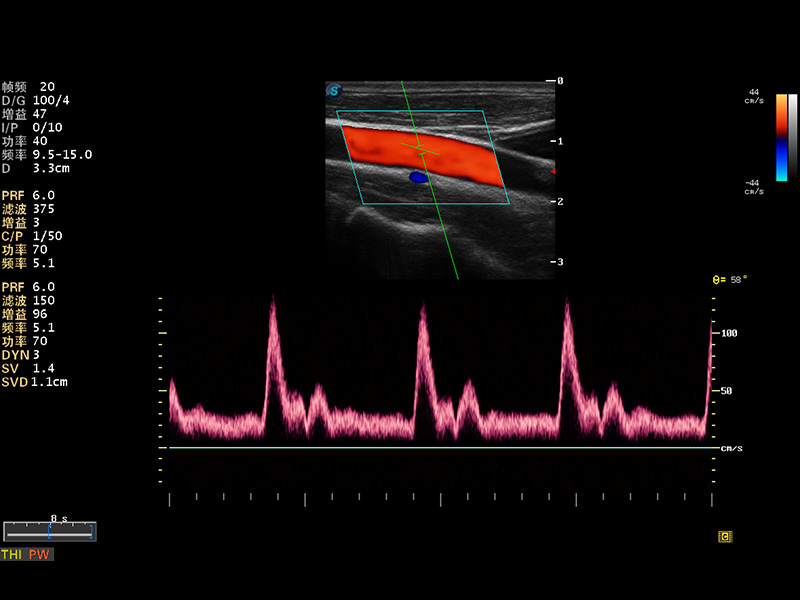

成像技術(shù)

多波束形成器

μ-Scan微米成像